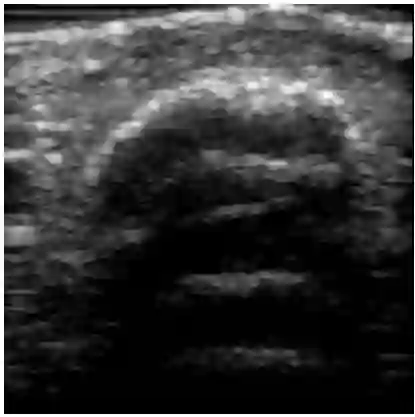

Chronic wounds including diabetic and arterial/venous insufficiency injuries have become a major burden for healthcare systems worldwide. Demographic changes suggest that wound care will play an even bigger role in the coming decades. Predicting and monitoring response to therapy in wound care is currently largely based on visual inspection with little information on the underlying tissue. Thus, there is an urgent unmet need for innovative approaches that facilitate personalized diagnostics and treatments at the point-of-care. It has been recently shown that ultrasound imaging can monitor response to therapy in wound care, but this work required onerous manual image annotations. In this study, we present initial results of a deep learning-based automatic segmentation of cross-sectional wound size in ultrasound images and identify requirements and challenges for future research on this application. Evaluation of the segmentation results underscores the potential of the proposed deep learning approach to complement non-invasive imaging with Dice scores of 0.34 (U-Net, FCN) and 0.27 (ResNet-U-Net) but also highlights the need for improving robustness further. We conclude that deep learning-supported analysis of non-invasive ultrasound images is a promising area of research to automatically extract cross-sectional wound size and depth information with potential value in monitoring response to therapy.